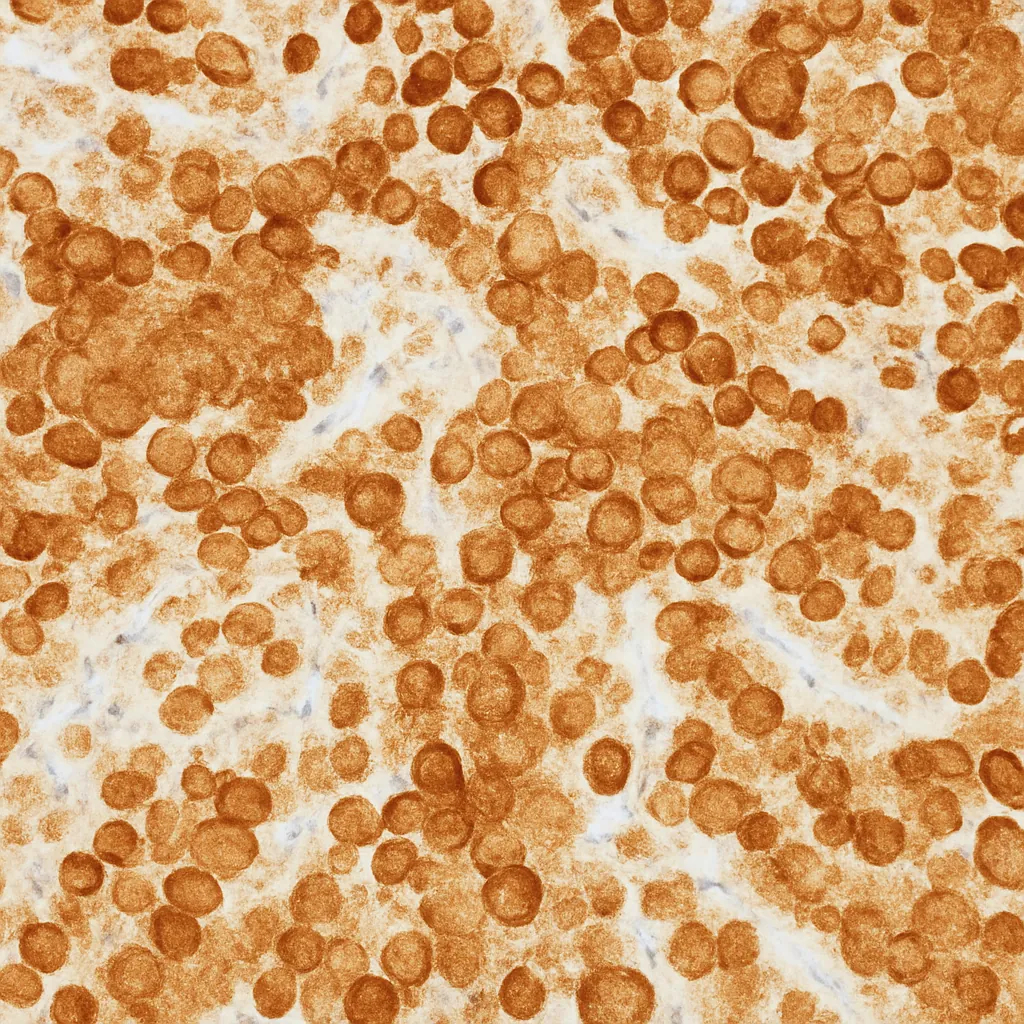

As a result, positive brown cytoplasmic staining strongly indicates a melanocytic origin.

- Clear brown cytoplasmic staining in positive cells